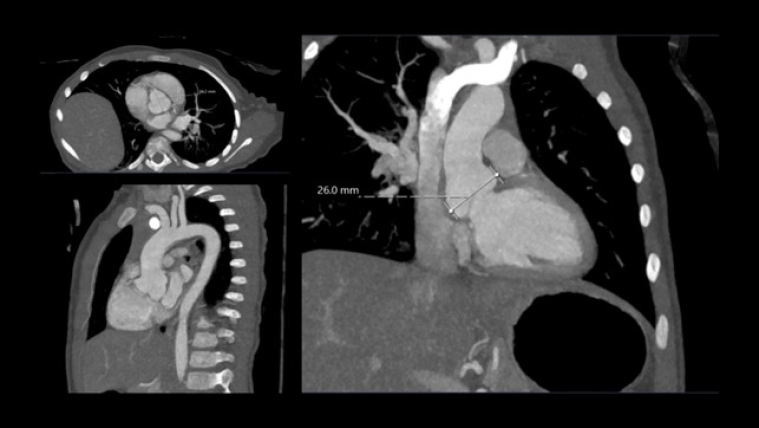

A month later she underwent cross sectional imaging. Her CT angiogram head to pelvis showed the aortic root was dilated and the thoracic aorta was elongated at the ascending and arch level, and tortuous with rightwards convexity in the descending portion. Z score Kaiser : sinus 24 x 23 mm (Z score + 4.1), ST junction 18 x 18 mm (Z score + 3.2), ascending aorta 18 x 16 mm (Z score + 3.1), transvers arch 15 x 14 mm (Z score +4.6), isthmus 9 x 9 mm (Z score + 0.5), diaphragmatic aorta 9 x 8 mm (Z score + 0.6). The brachio-cephalic arteries were dilated and tortuous.

She repeated a CT angiogram three years later that showed findings in keeping with her previous one. Z score kaiser : Sinus 26 mm (Z score + 4.7), ST junction 18 x20 mm (Z score + 2.5), ascending aorta 19 x 19 mm (Z score + 2.4), transvers arch 11 x 13 mm (Z score -0.1), isthmus 12.5 x 12.5 mm (Z score + 0.9), diaphragmatic aorta 11 x 11 mm (Z score + 1.1). Figure 4, table 1.

Vol 11  Figure 4. CT scan at 5 y.o. showing aorta dimension_Cardiovascular involvement.jpg